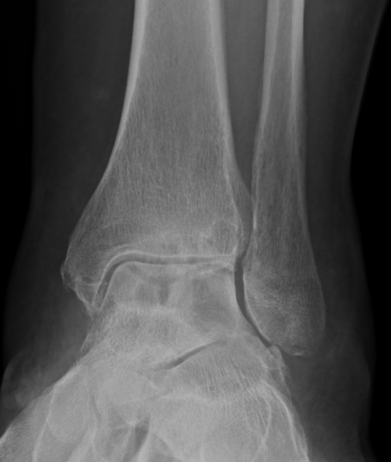

Xray - may show bony erosions

PVNS anterolateral gutter ankle

PVNS with ankle joint / talus erosion